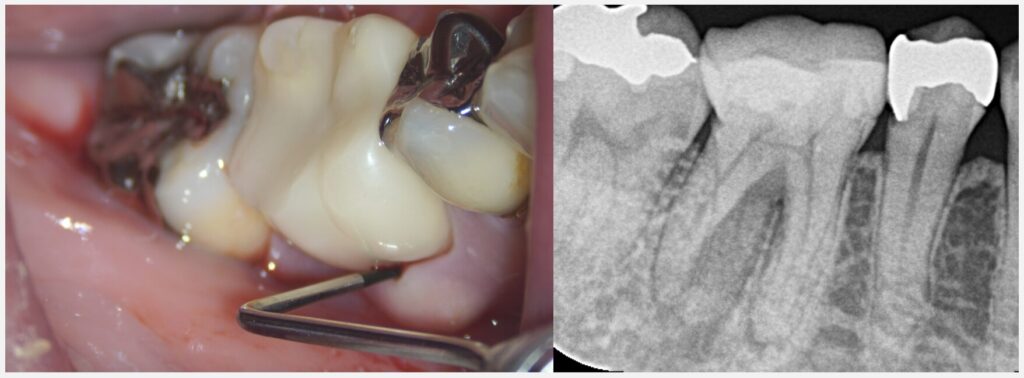

お疲れ様でした。拝見したところ、まず歯の神経は完全に死んでしまっている歯髄壊死という状態です。

そして、CTを拝見したところ、根の周りの骨の吸収がとても大きい状態です。根の先の膿の初期は骨の中にとどまっていますが、進行すると歯茎周りの骨にまで吸収が進み、そうすると今回のように歯茎の腫れや深い歯周ポケットへとつながります。ただ、⚫️⚫️様はお口全体を見ると歯周病の傾向はあまりなさそうなので、おそらくこの深いポケットは歯周病というよりも、歯の根の問題によるものと考えられます。

今回一番問題となるのが、歯の根が強く曲がっていて、根管も狭窄して細くなっている点です。非常に珍しいというわけではありませんが、慎重に治療を進めないと、ファイル破折という治療器具が根の中で折れる可能性があります。